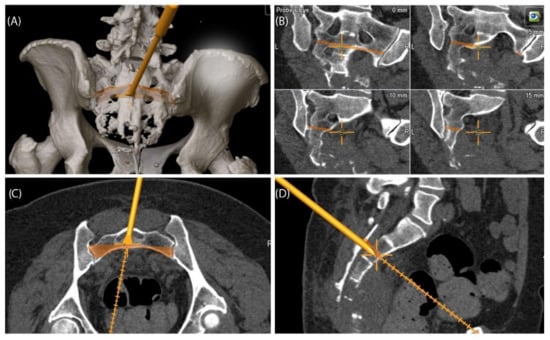

A 49-year-old female patient was diagnosed with an unclear sacral/coccygeal mass that was painful on palpation. The patient reported load-dependent coccydynia for 6–7 months with no typical radiculopathy, intact sensorimotor function, and regular fecal/urinary continence. After biopsy, high-grade osteoblastic osteosarcoma was diagnosed, and four cycles of neoadjuvant chemotherapy were administered according to the EUROBOSS protocol. Navigated resection of the sacral region S2/S3 to S5, including the coccyx (Figure 7), reconstruction of the defect of the rectal intestinal wall and reconstruction using a Vicryl mesh loaded with gentamycin chains, were conducted. Histopathologically, a R0 resection with a regression degree of 4 according to Salzer–Kuntschik was confirmed. Incontinence remained due to the resection of the sacral nerve roots. Because of reduced physical status, chemotherapy was not continued postoperatively.

Figure 7. Case 4: Segmentation and resection plane planning of a high-grade osteoblastic osteosarcoma of the sacrum; cross-sectional segmentation (AC) and 3D model with the resection plane as the volume (gray) (D,E).